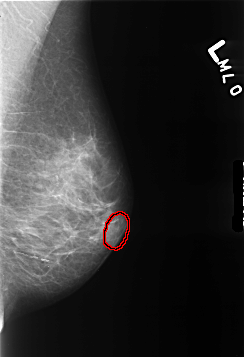

B_3445_1.LEFT_MLO

LEFT_MLO LINES 4280 PIXELS_PER_LINE 2920 BITS_PER_PIXEL 12 RESOLUTION 50 OVERLAY

FILE: B_3445_1.LEFT_MLO.OVERLAY

TOTAL_ABNORMALITIES 1

ABNORMALITY 1

LESION_TYPE MASS SHAPE LYMPH_NODE MARGINS N/A

ASSESSMENT 2

SUBTLETY 3

PATHOLOGY BENIGN_WITHOUT_CALLBACK

TOTAL_OUTLINES 1

BOUNDARY